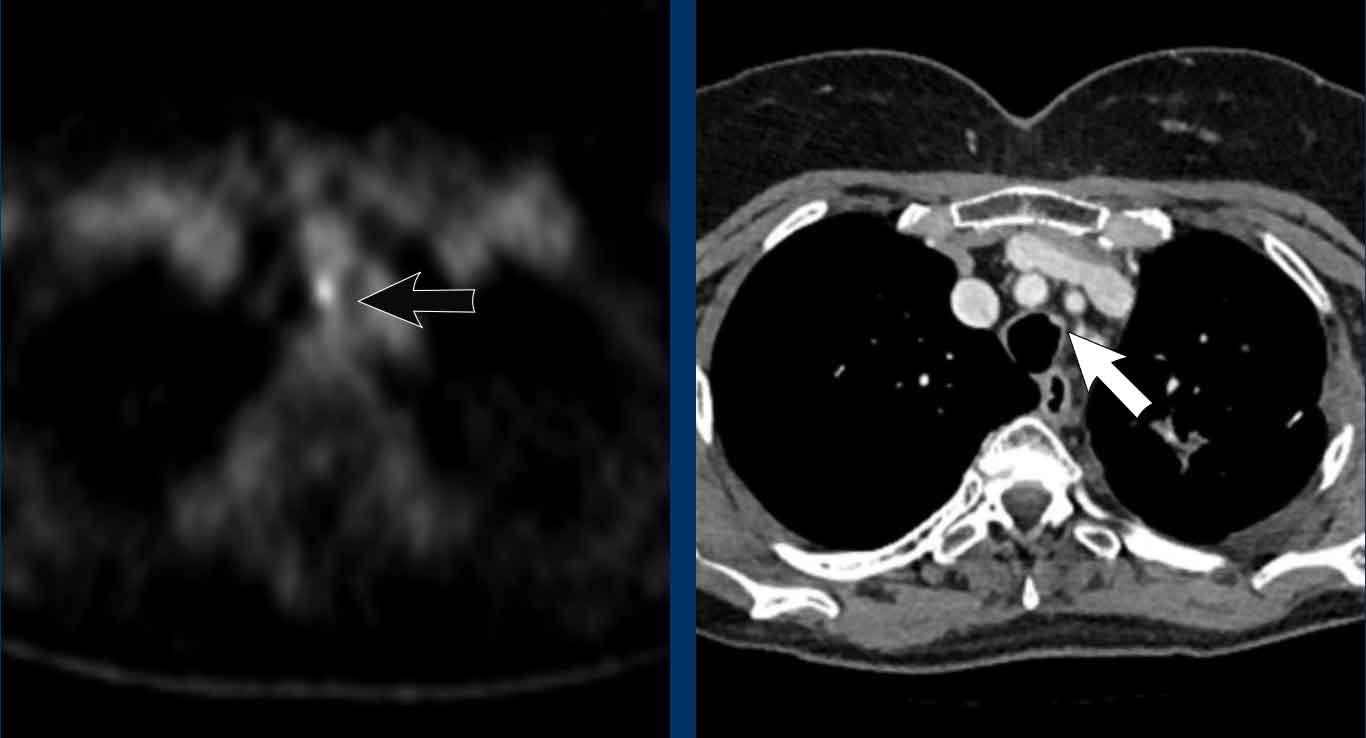

Hình ảnh

Dày thành lan tỏa toàn chu vi của khí quản và các phế quản trung tâm kèm tăng hấp thu trên xạ hình FDG-PET (mũi tên xanh) ở bệnh nhân nam 72 tuổi sau mở khí quản do biến chứng phẫu thuật cắt tuyến giáp.

Về mặt lâm sàng được xếp loại là nhiễm trùng độ thấp, mặc dù không phân lập được tác nhân gây bệnh đặc hiệu nào.